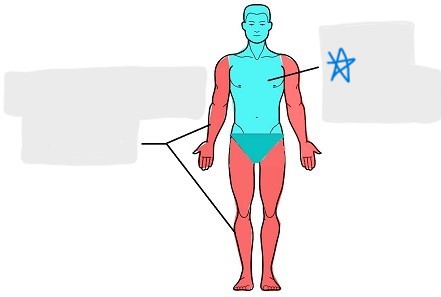

axial

appendicular

acromial

brachial

antecubital

olecranal

antebrachial

carpal

manus

coxal

femoral

patellar

popliteal

crural

sural

peroneal

calcaneal

plantar